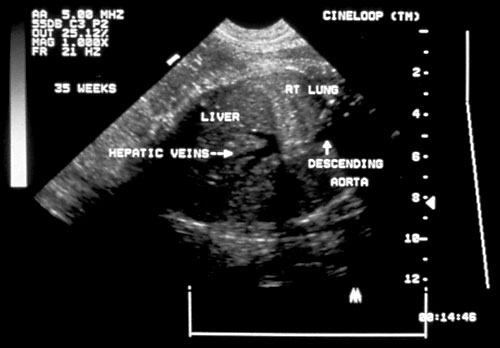

- Diaphragms — visualize in sagittal plane.

Normal diaphragm seen below right lung and above the liver in the middle of the picture with the hepatic veins diving below diaphragm. - Abdominal circumference.